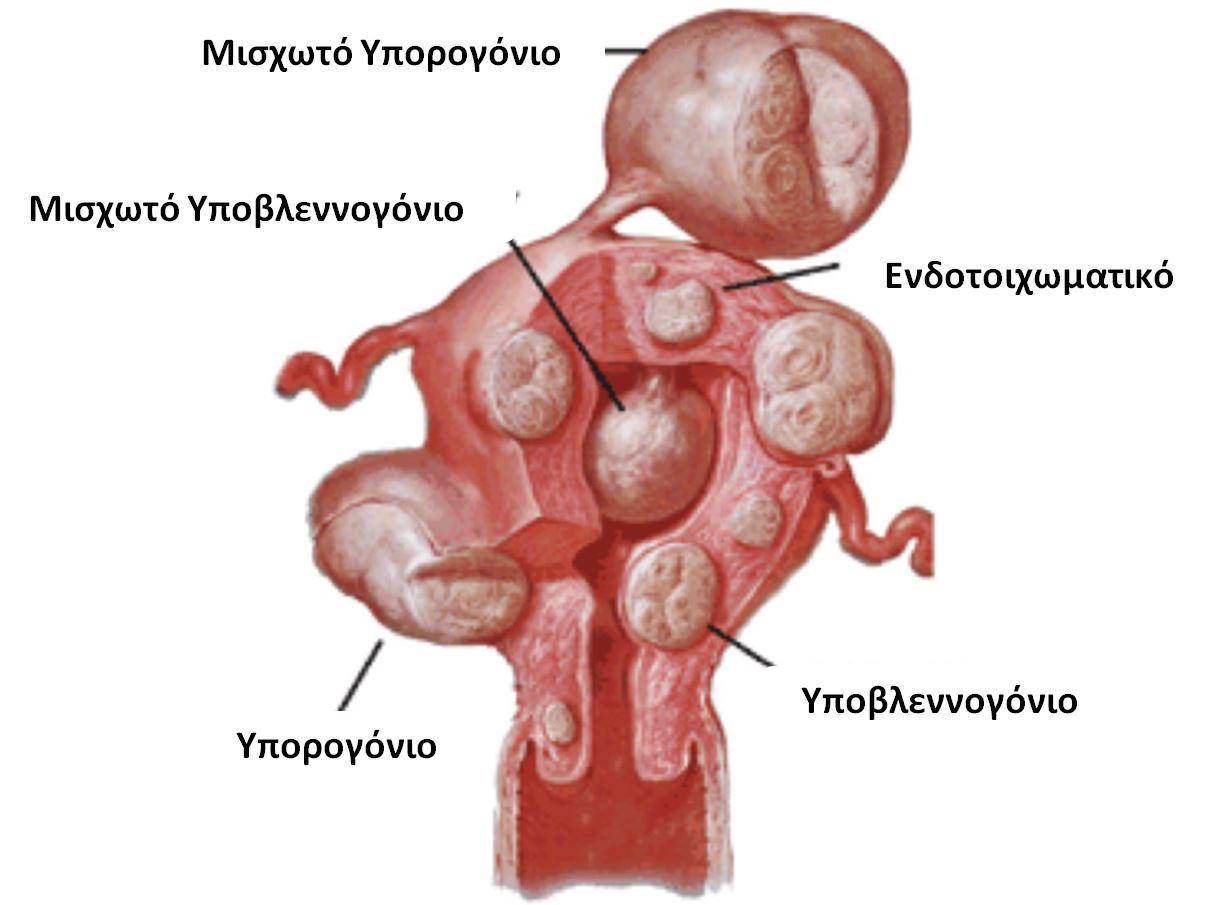

Ινομυώματα: Ένας ύπουλος εχθρός της γονιμότητας ΓΕΩΡΓΙΟΣ ΠΑΡΤΣΙΝΕΒΕΛΟΣ, MD, PhD Μαιευτήρας-Γυναικολόγος Διδάκτωρ Πανεπιστημίου Αθηνών Εξειδικευθείς στην Υποβοηθούμενη Αναπαραγωγή & Ελάχιστα Επεμβατική Χειρουργική Επιστημονικός Συνεργάτης Μονάδας Υποβοηθούμενης Αναπαραγωγής Institute of LIFE […]

Ινομυώματα: Ένας ύπουλος εχθρός της γονιμότητας ΓΕΩΡΓΙΟΣ ΠΑΡΤΣΙΝΕΒΕΛΟΣ, MD, PhD Μαιευτήρας-Γυναικολόγος Διδάκτωρ Πανεπιστημίου Αθηνών Εξειδικευθείς στην Υποβοηθούμενη Αναπαραγωγή & Ελάχιστα Επεμβατική Χειρουργική Επιστημονικός Συνεργάτης Μονάδας Υποβοηθούμενης Αναπαραγωγής Institute of LIFE […]